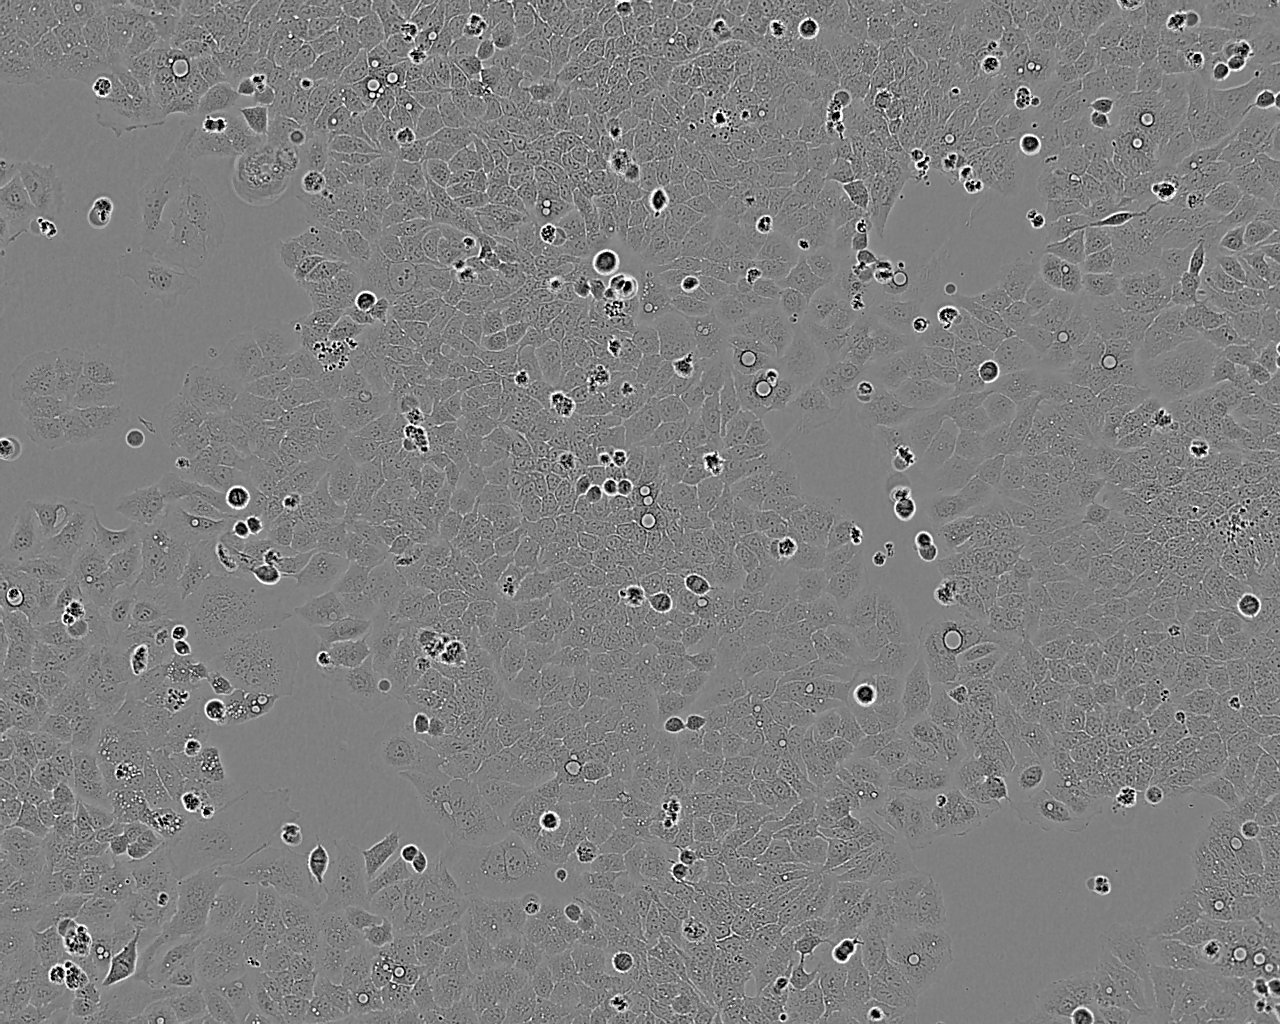

Ishikawa人子宮內膜癌細胞(STR鑒定正確)

• 形態(tài)特征: 上皮細胞樣

• 生長特性: 貼壁